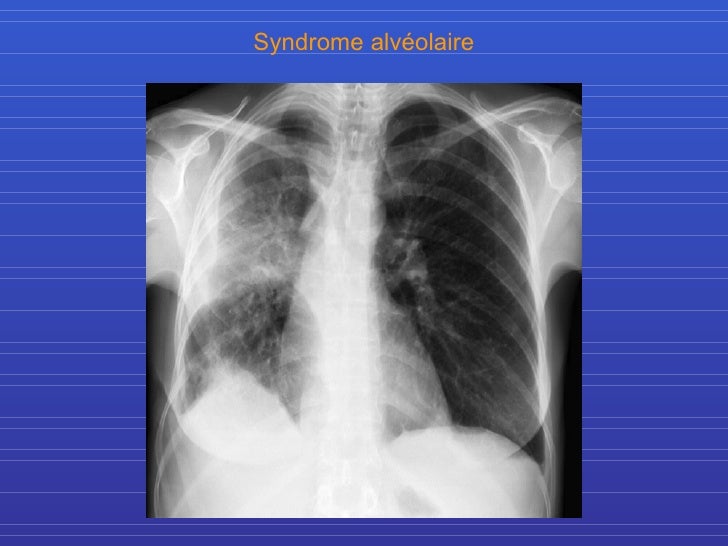

Semio radio thorax Radio Thorax Slideshare By the end of the lecture you should be able to : Normal radiographic anatomy of the thorax • obtaining a good thoracic radiograph • review anatomy • case examples obtaining a good thoracic radiograph • good quality image improves. Radiological anatomy of thorax dr. Vohra pleura is a double layered membrane that invests both lungs, lies on either side. Radio Thorax Slideshare.